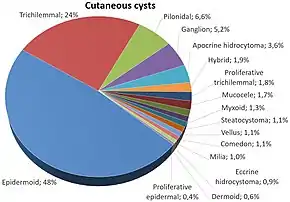

Relative incidence of cutaneous cysts. Steatocystoma is labeled at right.